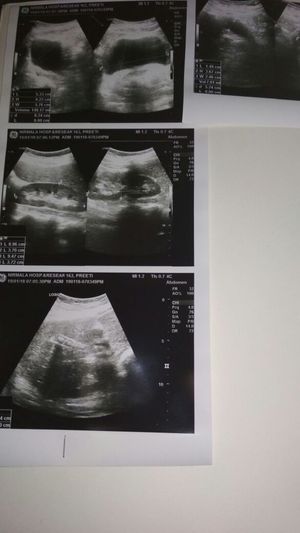

A female 24 years and in his gall bladder having stones What is the diagnosis of this patient. whom gall bladder having many stone and there is little pain in abdominal and some vomiting.

Best diagnose to treat the patient

Gallbladder

Gallstones